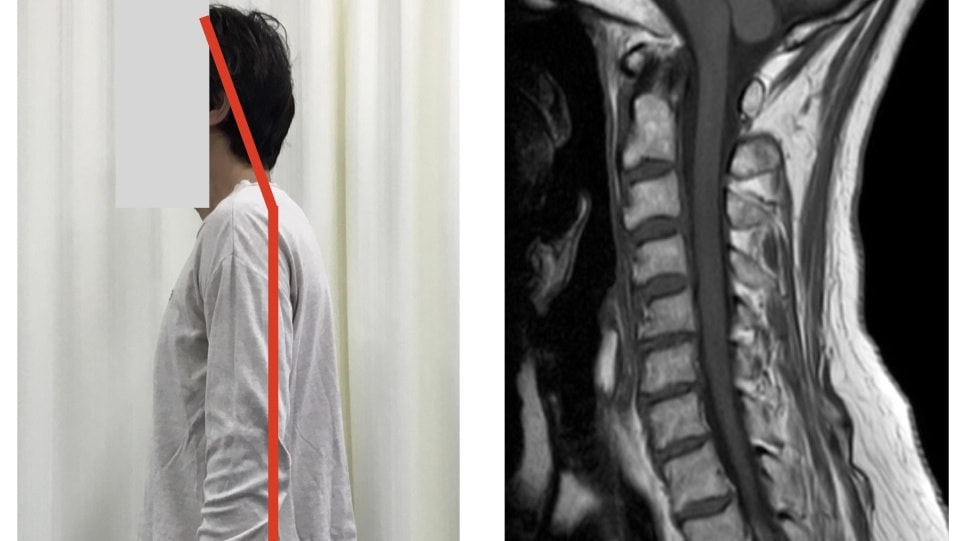

頚椎は、頭部を支えたり衝撃吸収を行う為に、前方へ弯曲しています。

これが「何かしらの影響」により骨の位置異常が起こると、「ストレートネック」や「頚椎ヘルニア」といった障害に繋がっていきます。

この「何かしらの影響」は、日常生活動作(長時間のデスクワークやスマホ使用など)や癖も関係しており、頚椎にある場合もあれば背部や肩など別部位からの問題で発生することもあるため、何処に原因があるかを明確に判断していく必要があります。